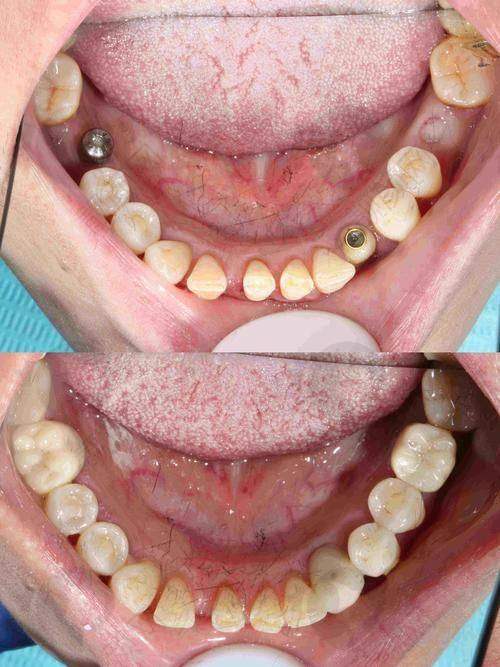

刘伟德种植牙实例

实例一:患者李先生,由于意外导致牙齿缺失,重度影响了他的咀嚼功能和面部美观。李先生来到大连医 科 大学附属第二医院口腔科找到刘伟德医生。刘医生经过详细的检查和评估,为李先生制定了种植牙方案。在种植过程中,刘医生操作精细,手术非常顺利。术后,李先生按照刘医生的指导进行护理,种植牙特别快就修复了良好的状态,李先生的咀嚼功能得到了极大的改善,面部也修复了往日的自信。

实例二:张女士因年龄增长,多颗牙齿脱落,生活质量受到了较大影响。她慕名找到刘伟德医生。刘医生根据张女士的口腔情况,为她设计了多颗种植牙的方案。整个种植过程中,刘医生充分考虑了张女士的身体承受能力,采用了精良的种植技术,减少了手术创伤。术后,张女士的种植牙成效非常理想,她又能像以前一样享受美食了。